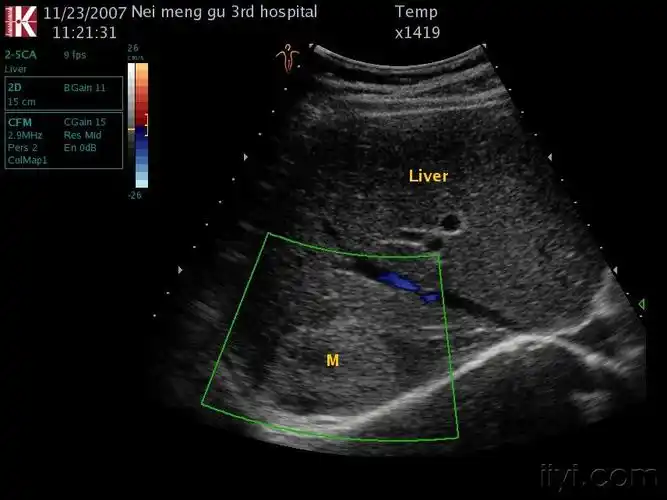

肝内强回声团(血管瘤?肝占位?

肝血管瘤?还是ca?

后伴声影的肝内血管瘤,请高手指点 - 超声医学讨论版 - 爱爱医医学

肝内低回声血管瘤? - 超声医学讨论版 -丁香园论坛